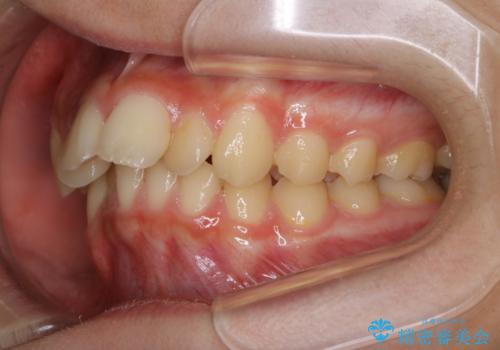

非抜歯で劇的に出っ歯を改善!インビザラインとカリエールの組み合わせ治療

- インビザライン カリエール

- 患者様、出っ歯のお悩みで来院されました。

骨格の分析を行ったところ上顎も出てはいるのですが、下顎が引っ込んでいる状態であるということがわかりました。

よって上顎の歯を抜いて治療をするのではなく、カリエールという器具を使用して下顎を前に引っ張り出しながら上顎を引っ込めるという治療を行うことにしました。